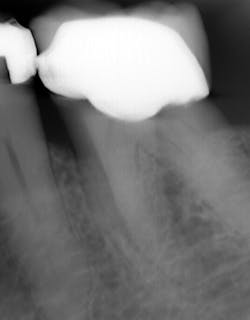

I see more complications and pathologies when using 3D tomosynthesis than I ever did with my old 2D images (figure 4). I can treat more because I can see more bone loss, interproximal caries, fractures, resorptions, abscesses, and more (figure 5).

In fact, twice today I was able to see something with Portray that wasn’t visible in the original 2D x-ray (figure 6). I don’t always take 2D images now, but I do when I think the case is straightforward or the patient has very little dental history. I often end up taking a tomosynthesis image just to be safe. With the 3D image I can scroll from buccal to lingual through the tooth and get much more data (figure 7). The new system has replaced my 2D PAs and bitewings.

Fortunately, 3D intraoral tomosynthesis found its way into the dental field. Based on the findings from a study out of the University of North Carolina, dentists who use 3D tomosynthesis for intraoral x-rays can detect approximately 36% more caries (figures 8 and 9).1 That’s tremendous!